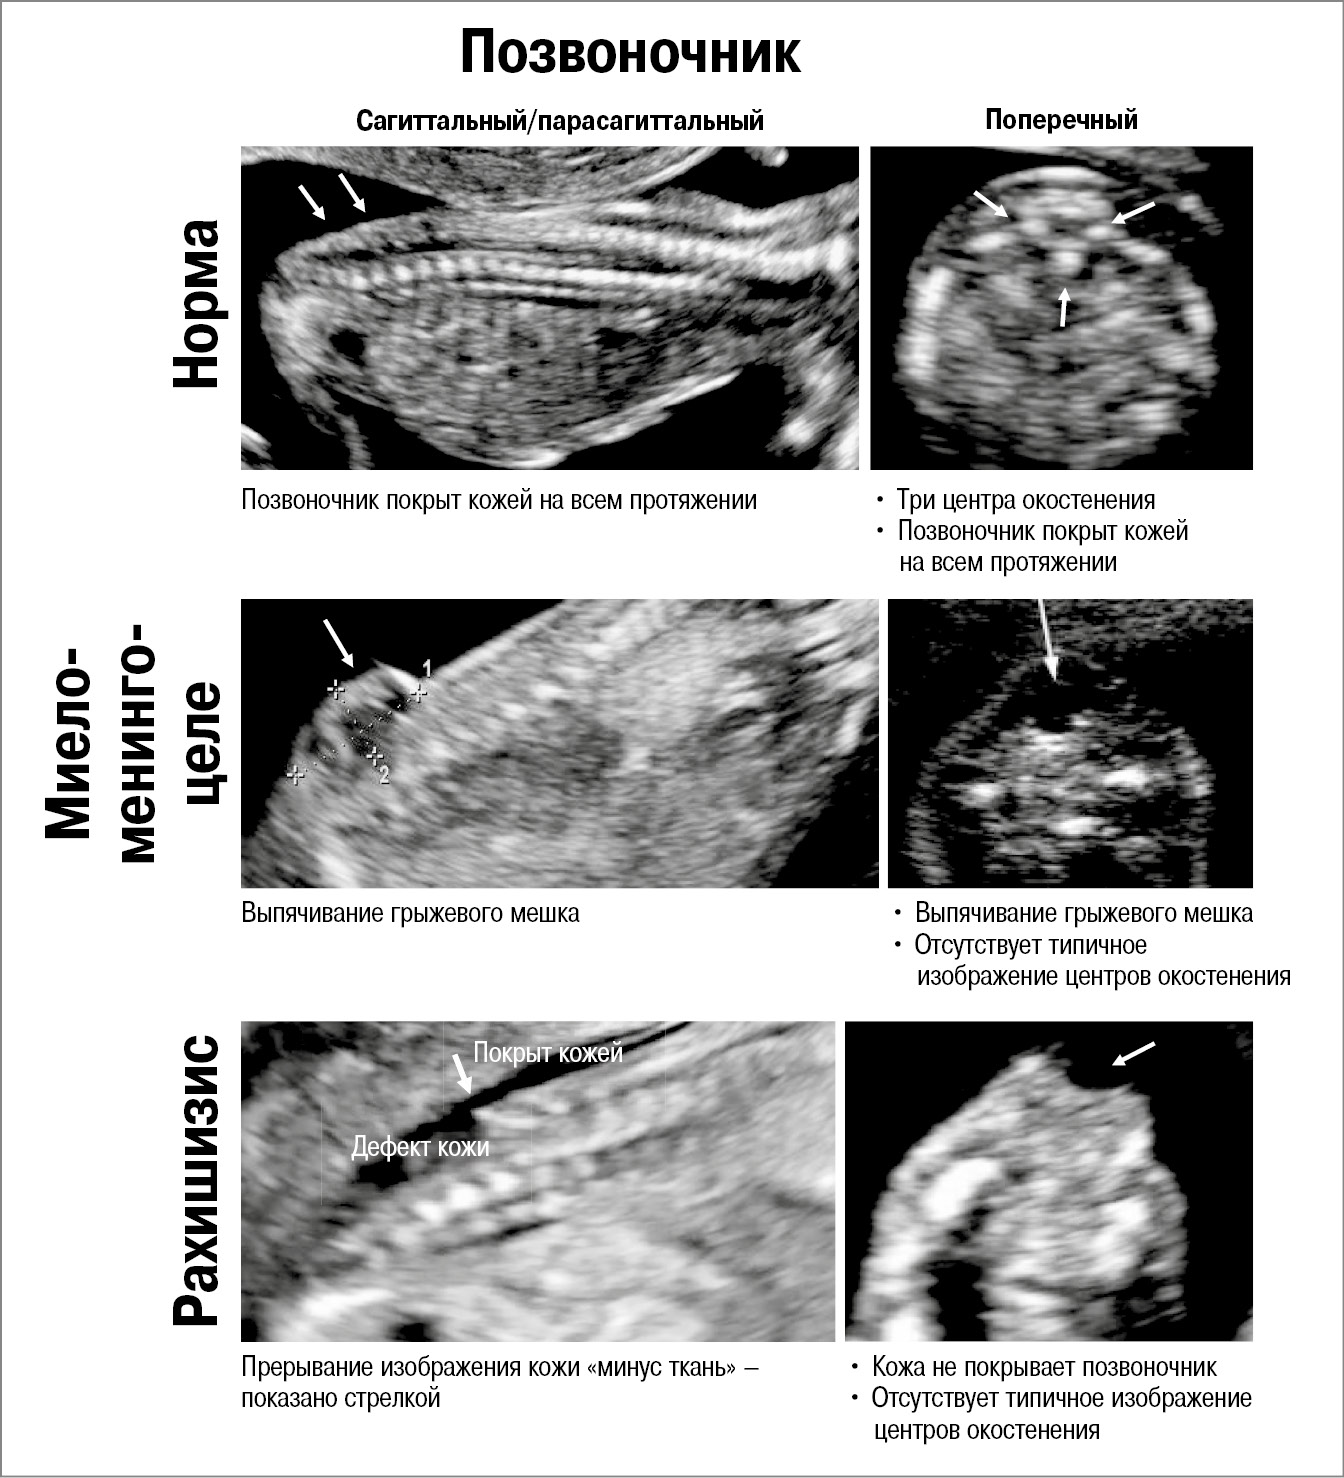

Позвоночник оценивается в трех срезах – сагиттальном, поперечном и коронарном (рис. 3). В норме позвоночник покрыт кожей на всем протяжении, визуализируются его 3 центра окостенения, отсутствует искривление. Эхографическими признаками открытого спинального дизрафизма являются следующие находки: дефект кожи, наличие грыжевого выпячивания, отсутствие типичного изображения центров окостенения. Дополнительно проводится поиск сочетанных патологических состояний, таких как искривление (кифоз/сколиоз), гемивертебра и др.

Рис. 3. Ультразвуковые признаки открытой spina bifida в I триместре беременности (11–14 нед). Оценка позвоночника.